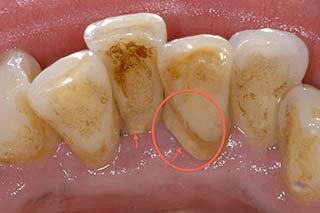

カラー写真だと一見したところ異常が無い様に思えますが、、、

歯肉を切開し骨をあらわにしたところ、最奥歯の骨の欠損が確認できます。